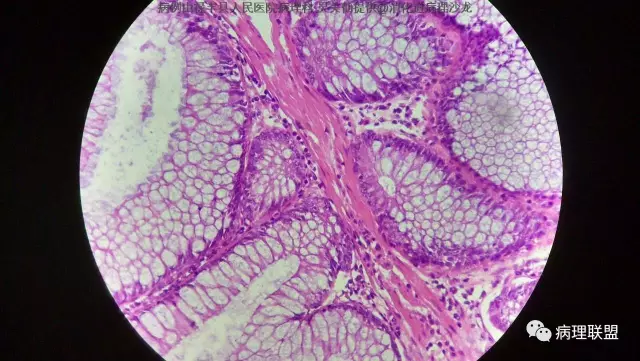

M/50 直肠(P-J息肉VS增生性息肉?)

P-J息肉?增生性息肉?请老师们看看!(病例由禄丰县人民医院病理科 吴美仙提供,致谢!)